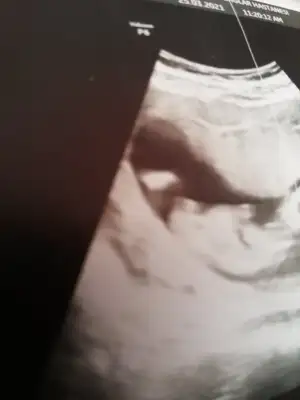

İkra meyra Sizce cinsiyeti nedir 13 hafta

Merhaba Ikra meyra Ikra meyra şu çıkıntı kafamı karıştırdı, nub mudur sizce?🙈 Sanırım ilk resimde bebek ters dönmüş ama kafası düz bakıyor, yanılıyor muyum acaba...😬